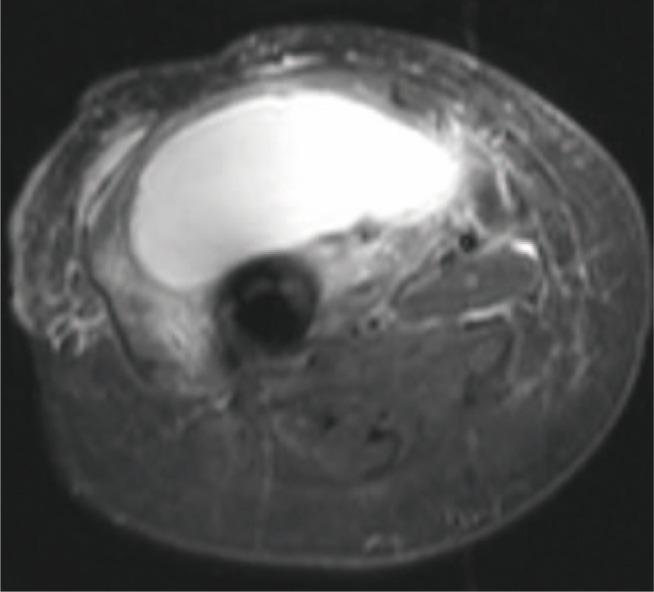

Periprosthetic joint infection (PJI) due to is rare. It frequently occurs patients receiving immunosuppressive medicine. We describe two periprosthetic infection of two immunocompromised patients. Both of patients were receiving azathioprine and prednisolone therapy. First patient presented six years after total hip arthroplasty with a huge abscess on her right thigh that was reached to femoral component through the lytic area of lateral femur. Second patient presented with drainage from his hip and he had undergone two-step revision surgery for PJI 3 months ago. There is no consensus in the treatment of periprosthetic salmonella infections. We prefer two-step revision surgery for these infections as previously described in the literature.